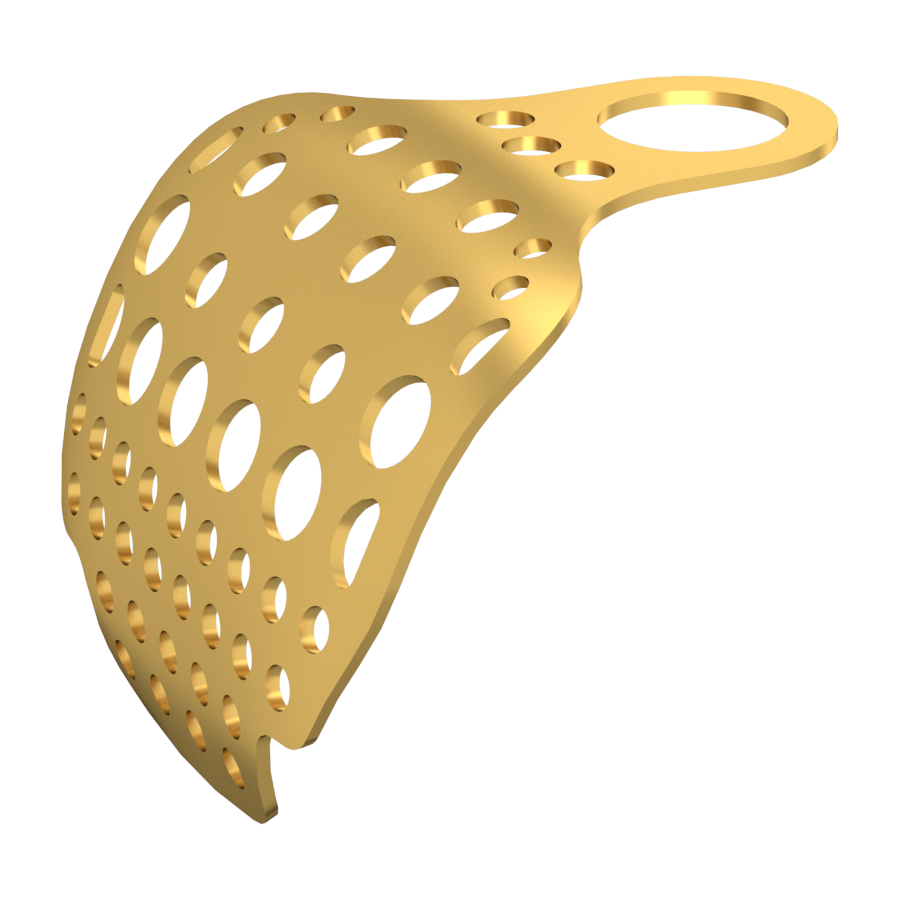

Our Titanium Mesh Membrane is designed to offer optimal support in guided bone regeneration (GBR) procedures, combining structural stability with excellent adaptability. The ultra-thin, anatomically contoured design allows for a comfortable fit and easy surgical handling, while maintaining strong support for the defect area. It can be easily trimmed and shaped to match various bone contours, making it a reliable and versatile choice in both simple and complex cases.

Key Features:

Easy to cut and shape: Allows for fast, precise contouring during surgery

Enhanced fixation: Designed to be used with bone tacks for stable placement

Ultra-thin design: Reduces foreign body sensation while ensuring structural strength

Anatomical curvature: Provides high intraoperative fit and reduces surgical time

Perforated (lightening) holes: Ensure good vascularization and promote blood supply to the regeneration site